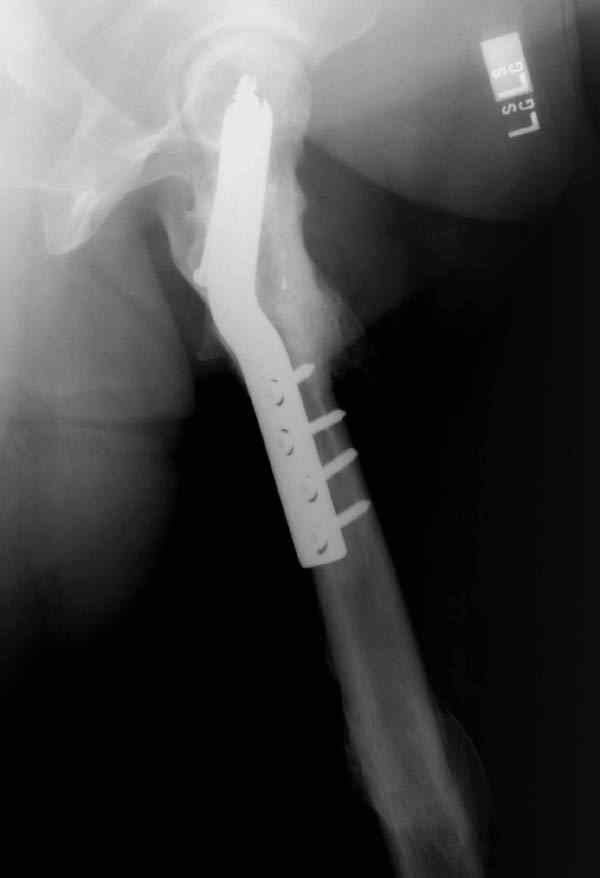

Наверно, вариант с вальгизирующей остеотомией с фиксацией blade plate или DHS более щадящий. А диафиз можно рефиксировать ретроградно. Или про эндопротезирование с очень длинной ножкой подумать.

Уважаемые коллеги. Благодарим за дискуссию. Мы решили выполнить комбинированную операцию - эндопротезирование тазобедренного сустава и ретроградный интрамедуллярный остеосинтез (одномоментно)